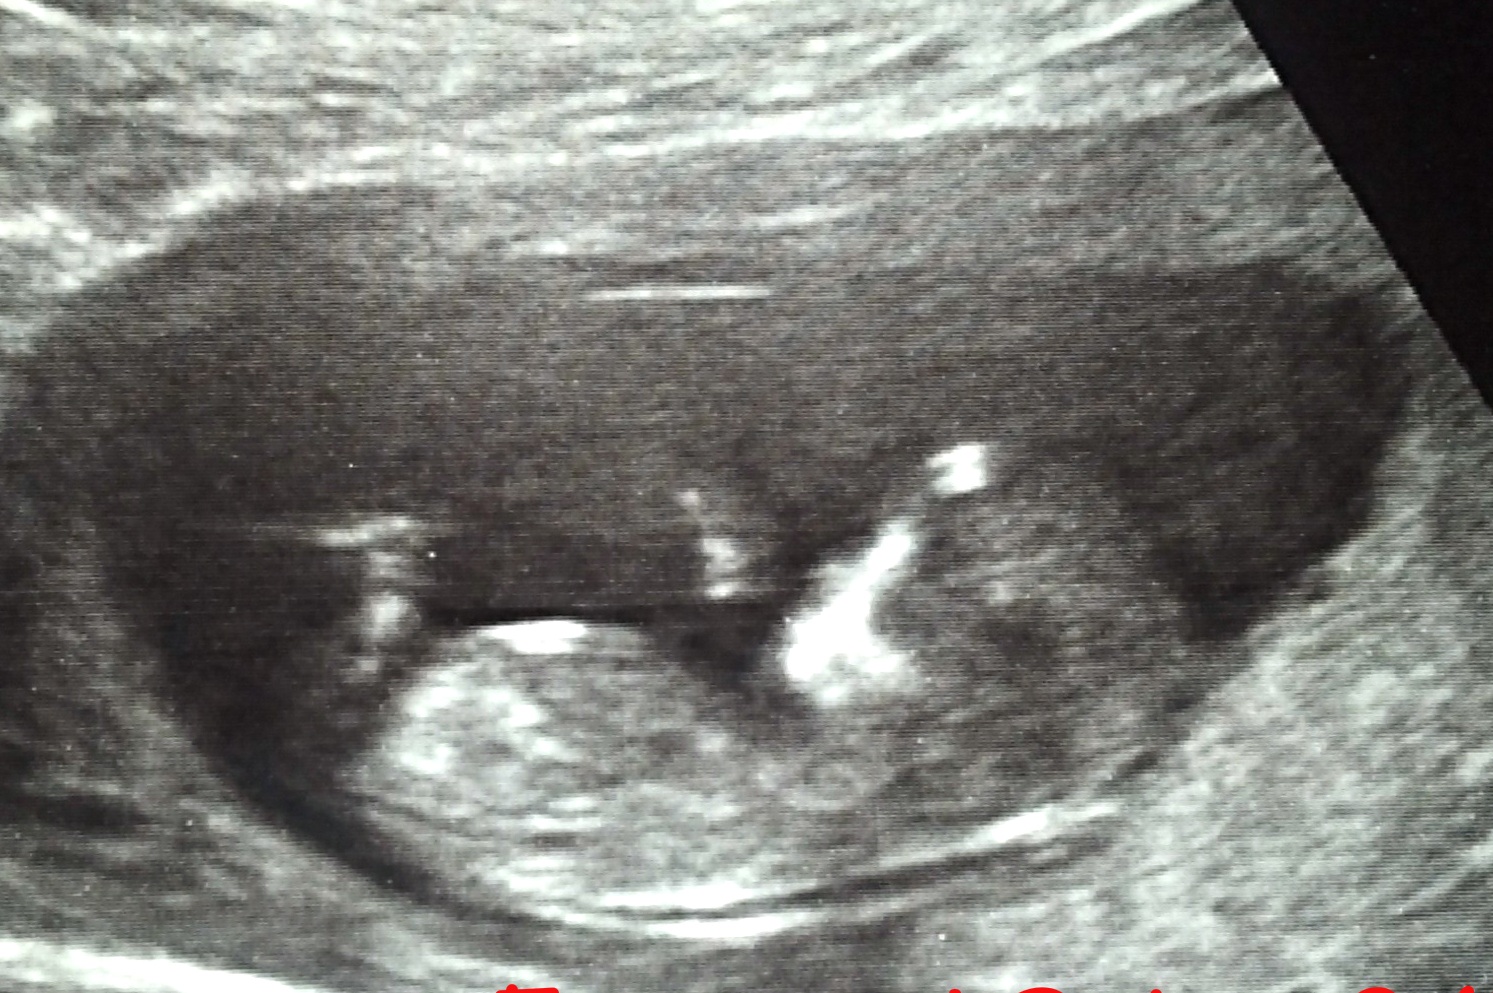

Here's my baby's u/s pic from 12w2d. I've tried to ultrasound myself at work (I'm a veterinarian), but haven't had good luck getting the correct position from baby. Anatomy scan is next Monday, but I'd be more than grateful for any nub guesses. TIA!Attachment 5017